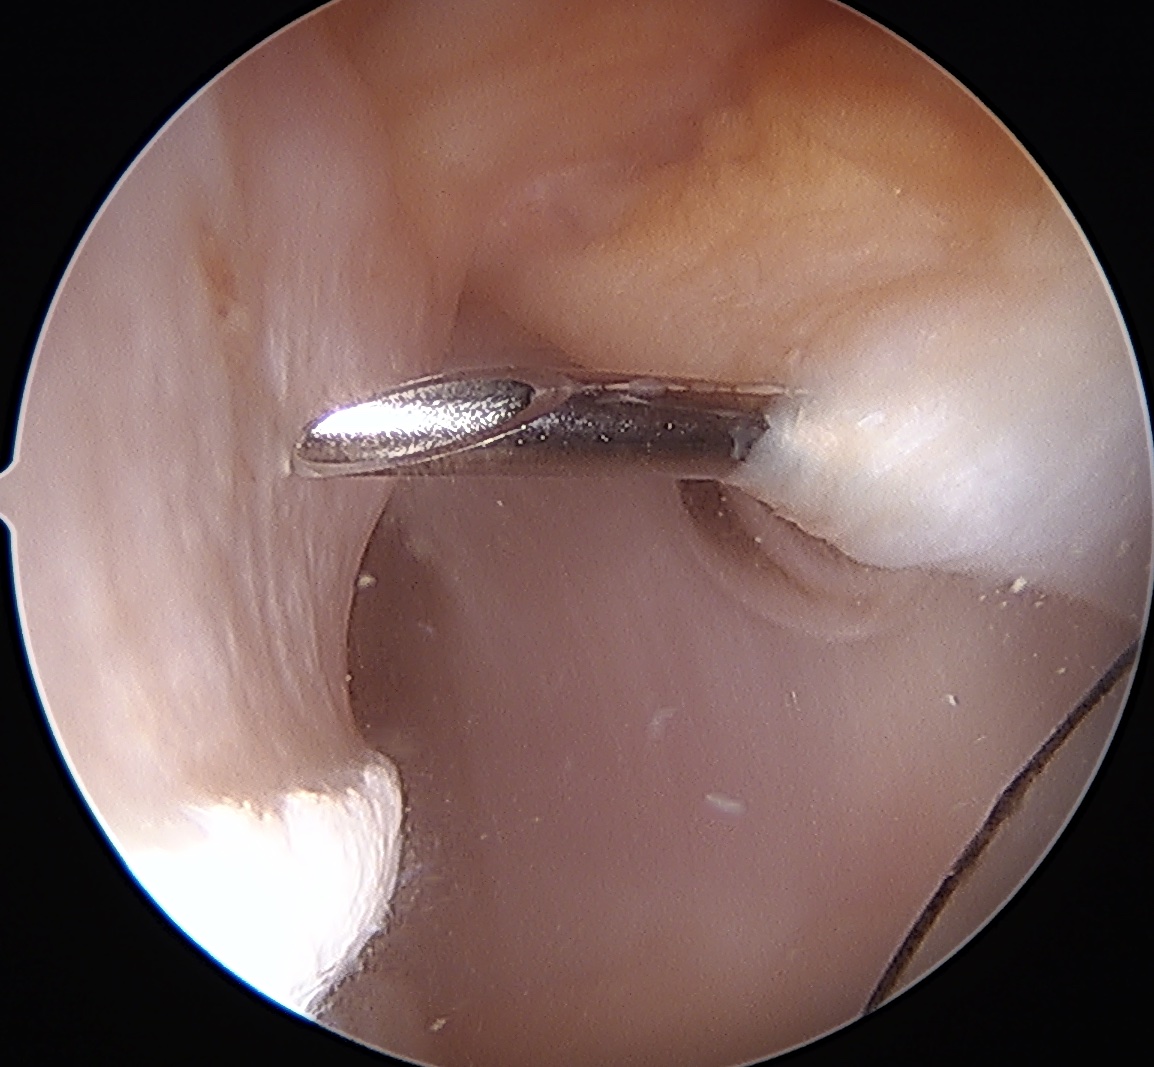

- can tie blind or put camera into subacromial space

Tying knots under direct vision in the subdeltoid space using double pulley technique

End result